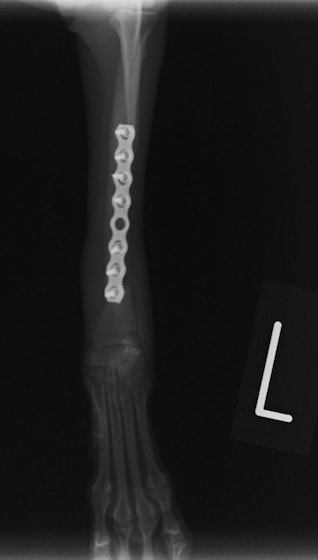

トイプードル 右遠位橈尺骨短斜骨折のALPSによる内固定

LCPは、スクリュー(ネジ)とプレート(金属の板)をロックする特殊な構造により骨折部位を固定する新しい世代のプレートシステムです。ひとつのホールでロッキングスクリューとスタンダードスクリューの使用を選択できるユニークな構造をしているため、骨折断端間の圧迫を目的とした従来型プレート固定法に加え、高い角度安定性を有するロッキングスクリューを用いた固定法の選択が可能です。従来のプレートシステムでは困難だった部分の骨折や癒合不全の症例に高い治療効果をもたらします。

7.1.5mmと薄いプレートのため、超小型犬にも使用しやすい